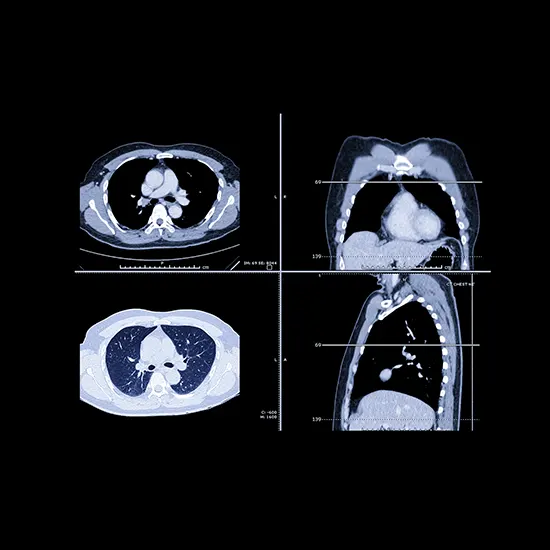

CECT Chest                                                7,000 3500

Test Type Lung Cancer Package

Lung Cancer Package test  (Cancer)